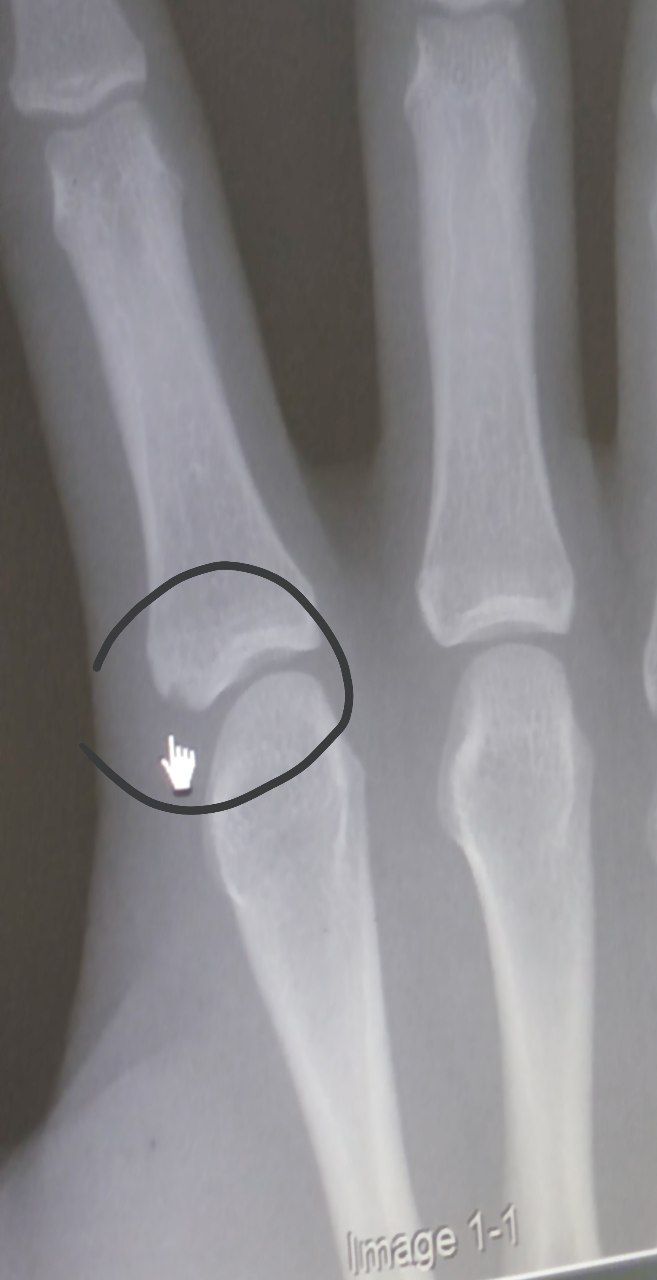

![]()

I don't think a doctor would look at this and say that growth is impossible for a 15.5 year old, so that makes me not believe his claim about seeing a doctor to begin with since his plates look open.

Deleted member 114712's xray and story makes little to no sense

View attachment 4323306

Correction* I also don't believe he grew 8-9cm, that's ridiculous, his plates aren't fused, but aren't open enough to grow that muchDeleted member 114712's xray and story makes little to no sense